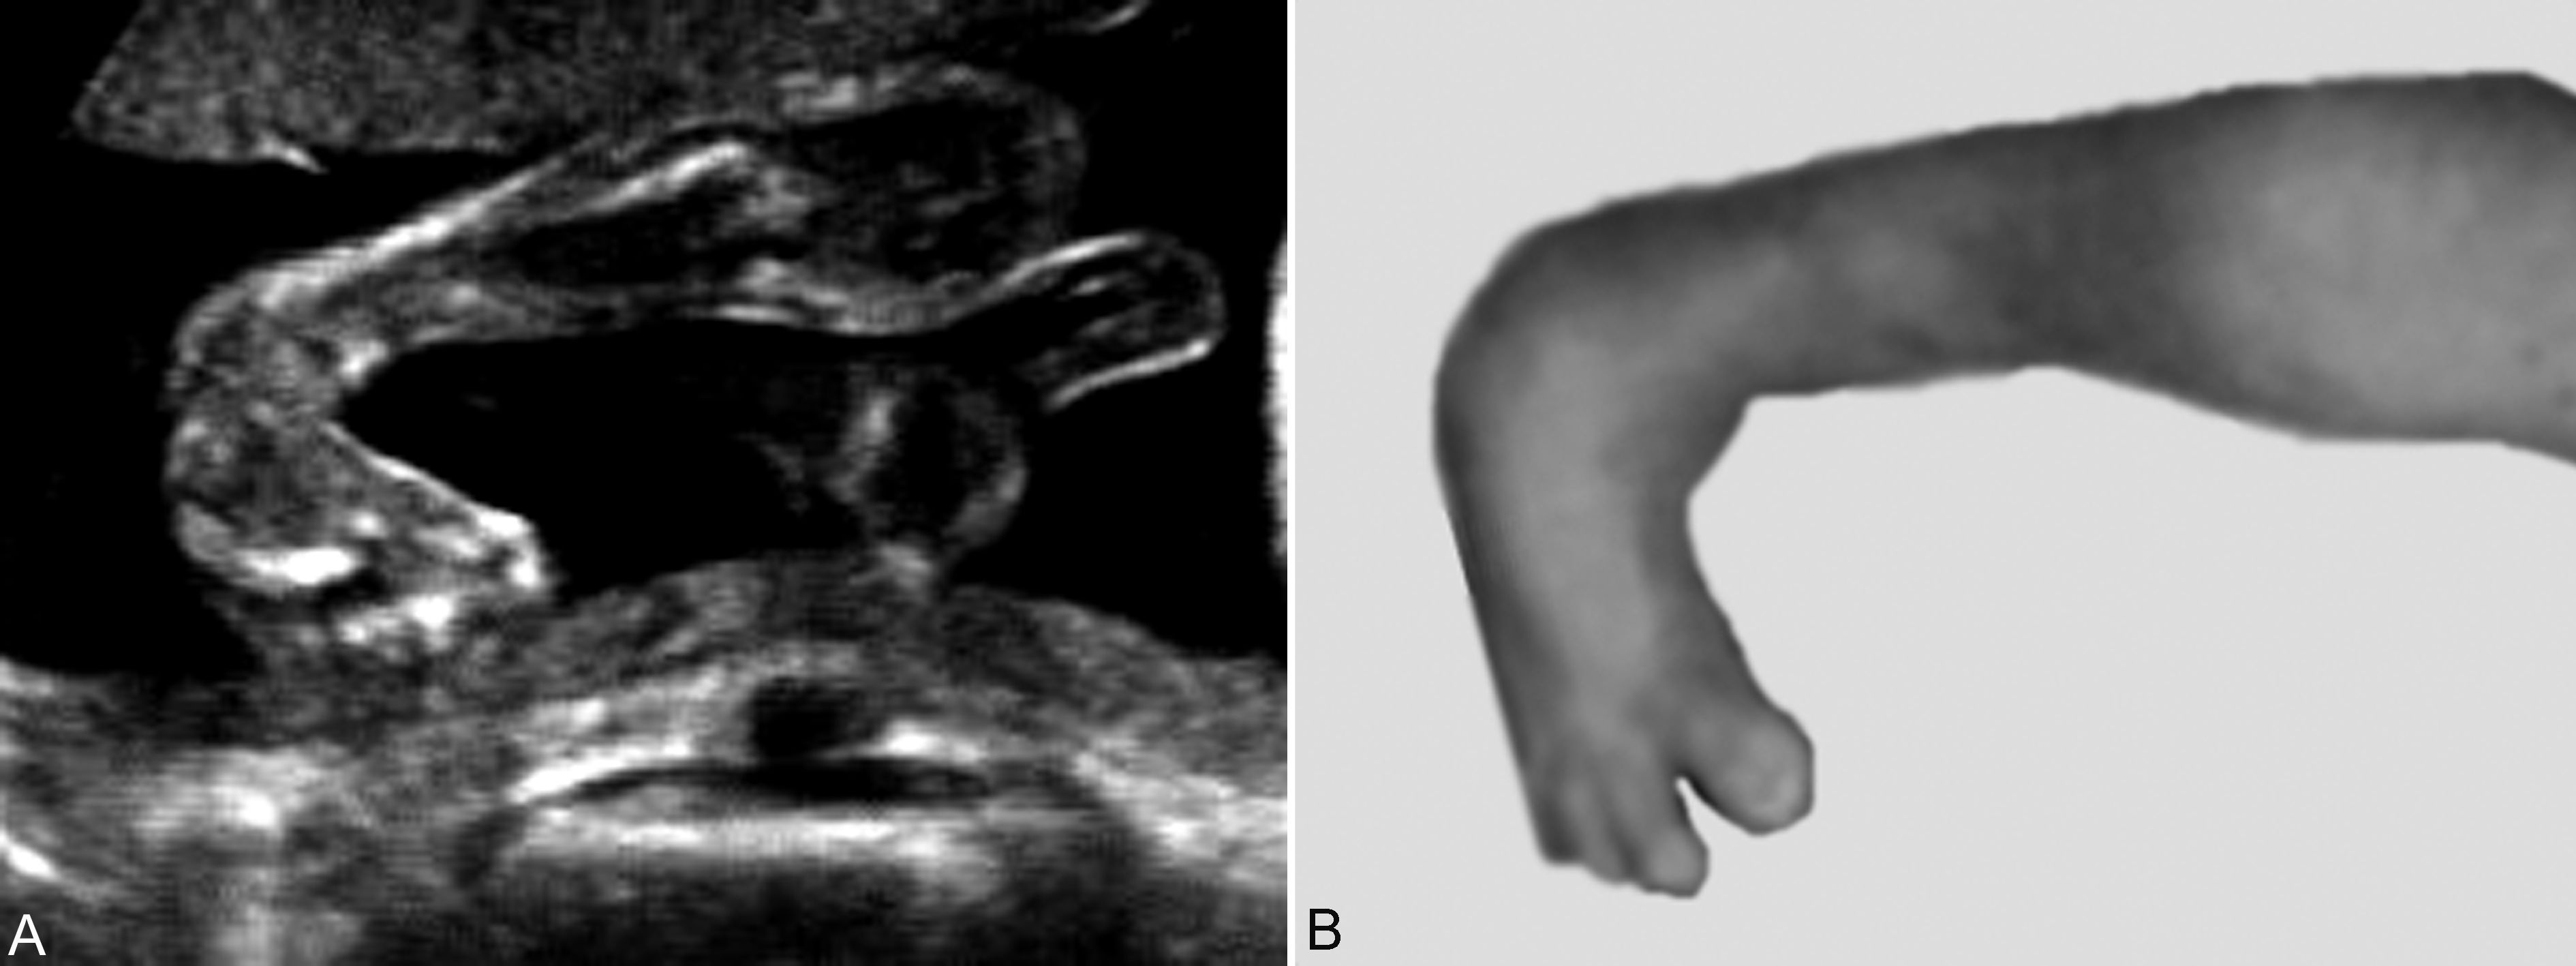

由于肢端部具有灵活的运动功能,屈、伸、内收、外翻、旋转等灵活多变,超声显像检查时显示的一种位置并不一定由发育异常引起,也可能处于一种临时的运动状态。反复多次的检查可能显示诸如多指(趾)、并指(趾)、短指(趾)、马蹄内翻足等畸形(图6),三维超声显像检查有助于对畸形的显示和判断。多数需要出生后检查明确诊断。

图6胎儿足内翻畸形(B为出生后胎足照片)